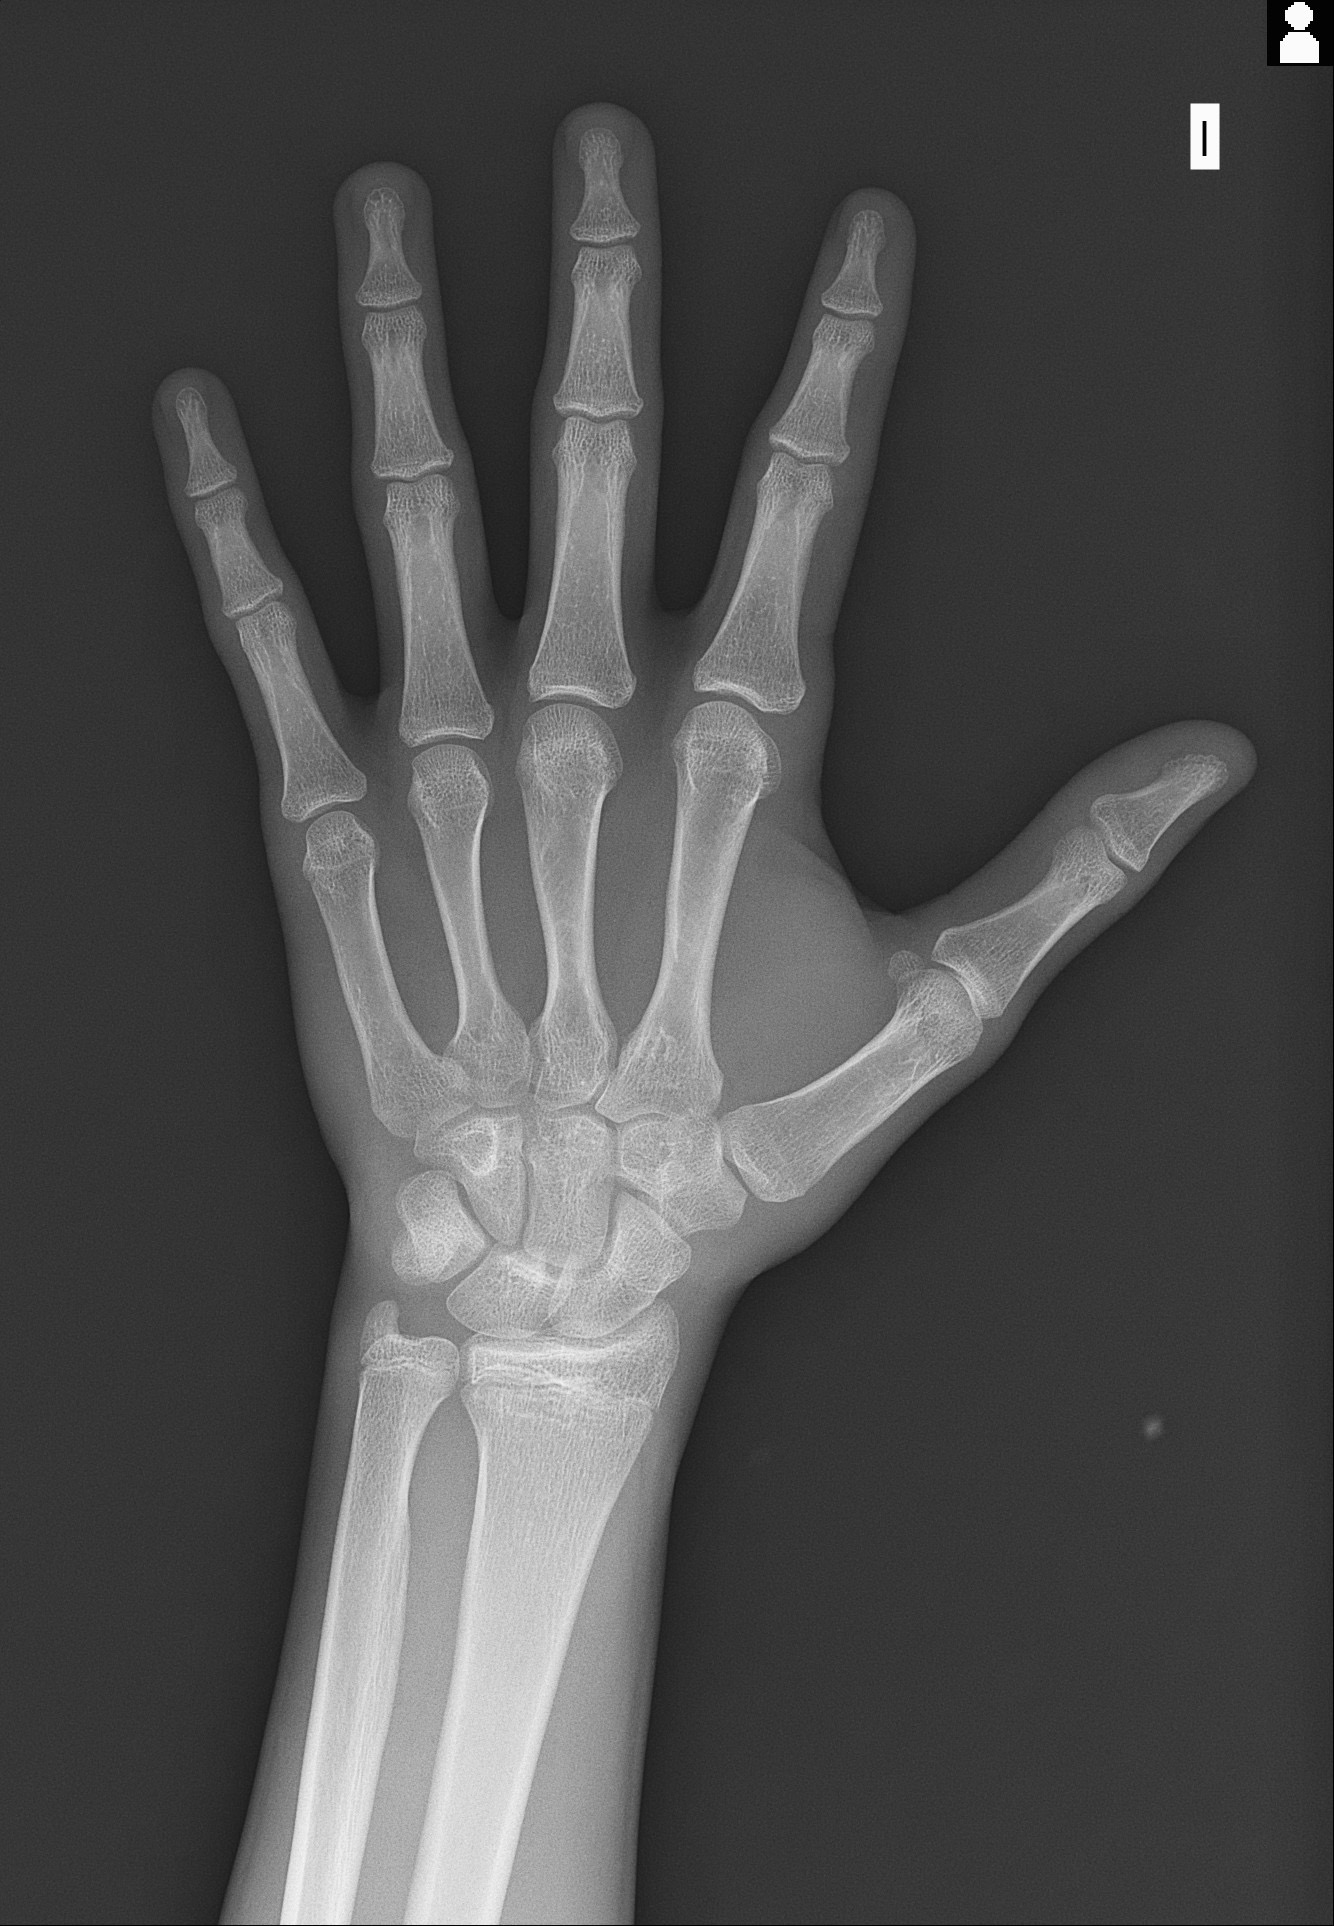

Is there any good chance that I would reap out +4 cm with using normal doses of hgh and ai that don’t put my health at extreme risk, considering these shitty as growth plates? I know I can get LL but that’s not the point of this thread right now